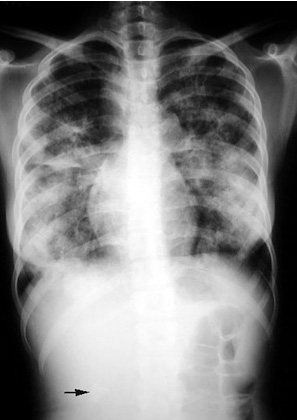

Sarcoidosis

Renal stone

Presented with renal stone and hypercalcemia